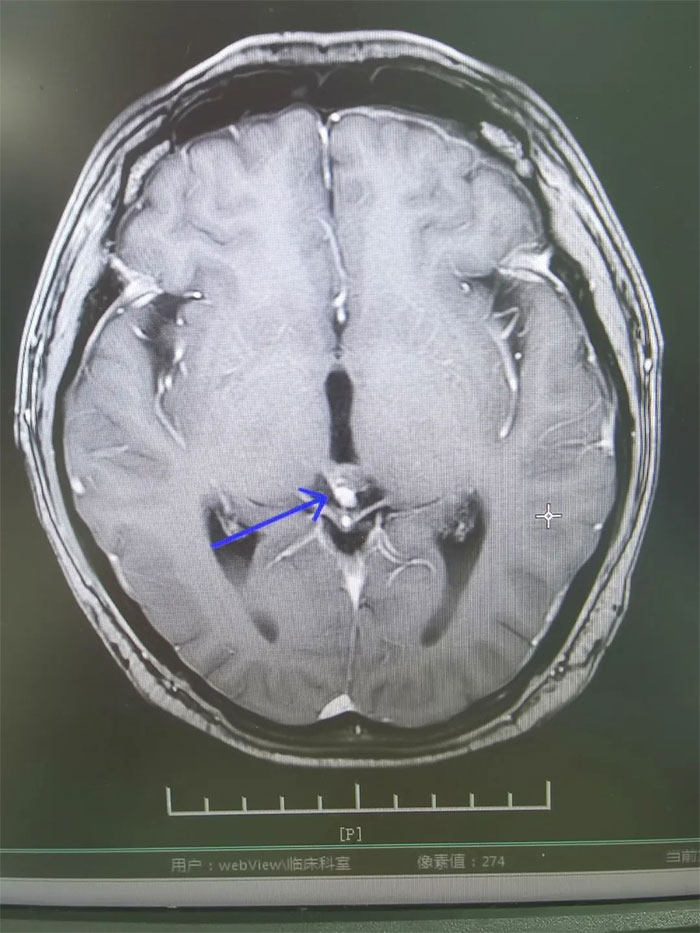

▲ 放疗后复查,病灶明显缩小

经过一个完整疗程的放疗,患者没有出现明显并发症,头痛、恶心呕吐症状得到缓解。复查MRI,影像显示病灶明显缩小,梗阻性脑积水消失。进一步完善检查评估后,小刚已顺利出院。眼见短时间内病情即得到控制,小刚对生活又重拾信心,表示一定会以积极的心态面对人生。